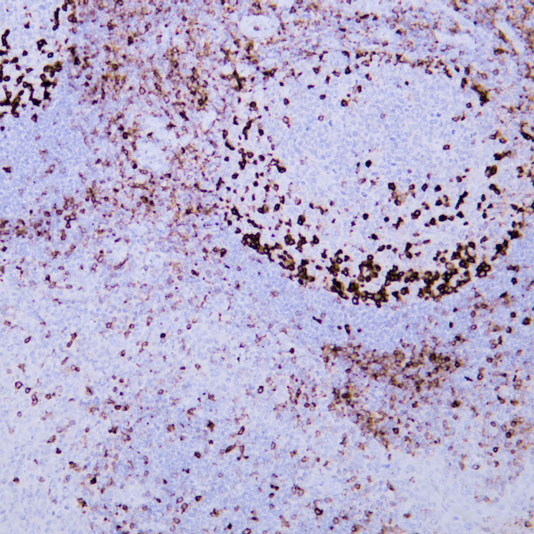

Explore Our Recommended Popular Products

30,000+ high- quality products available online

Primary Antibodies, Secondary Antibodies, mIHC Kits, ELISA Kits, Proteins, Molecular Biology Products,Cell Lines,Reagents ...